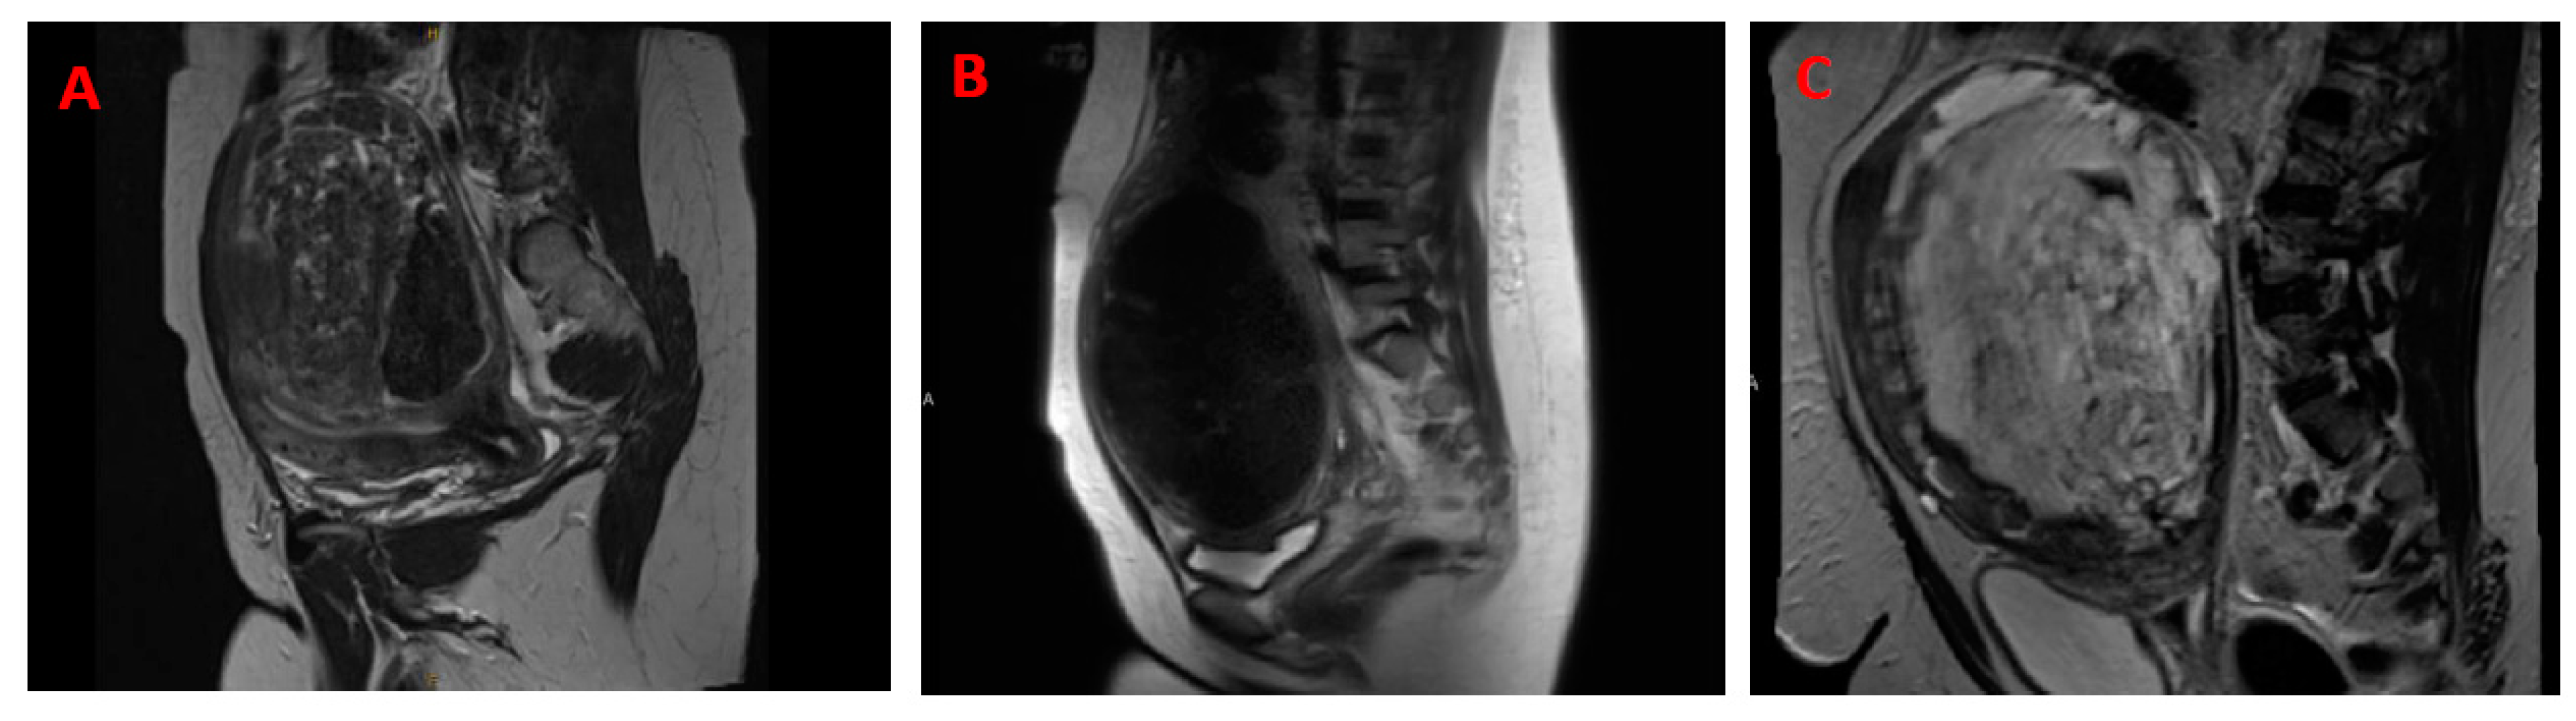

2. Differential Diagnosis of Uterine Leiomyosarcoma and Leiomyoma

2.1. Challenges with Differentiating Uterine Leiomyoma from Uterine Leiomyosarcoma

6.1. Clinical Diagnosis between Malignant Uterine Leiomyosarcoma and Benign Leiomyoma

6.1.2. Advanced Imaging—Artificial Intelligence and Machine Learning